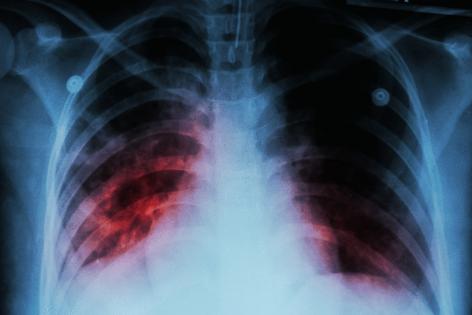

Tuberculosis is a bacterial infection with both active and latent stages. A person with active tuberculosis disease, which can be deadly, can spread the disease. A person with a latent infection can’t, but they can develop the disease at any point.